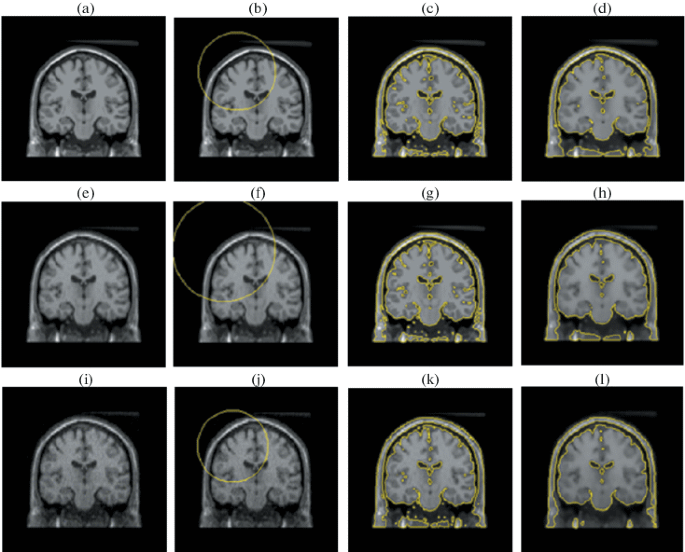

A Hybrid Segmentation Approach of Brain Magnetic Resonance Imaging